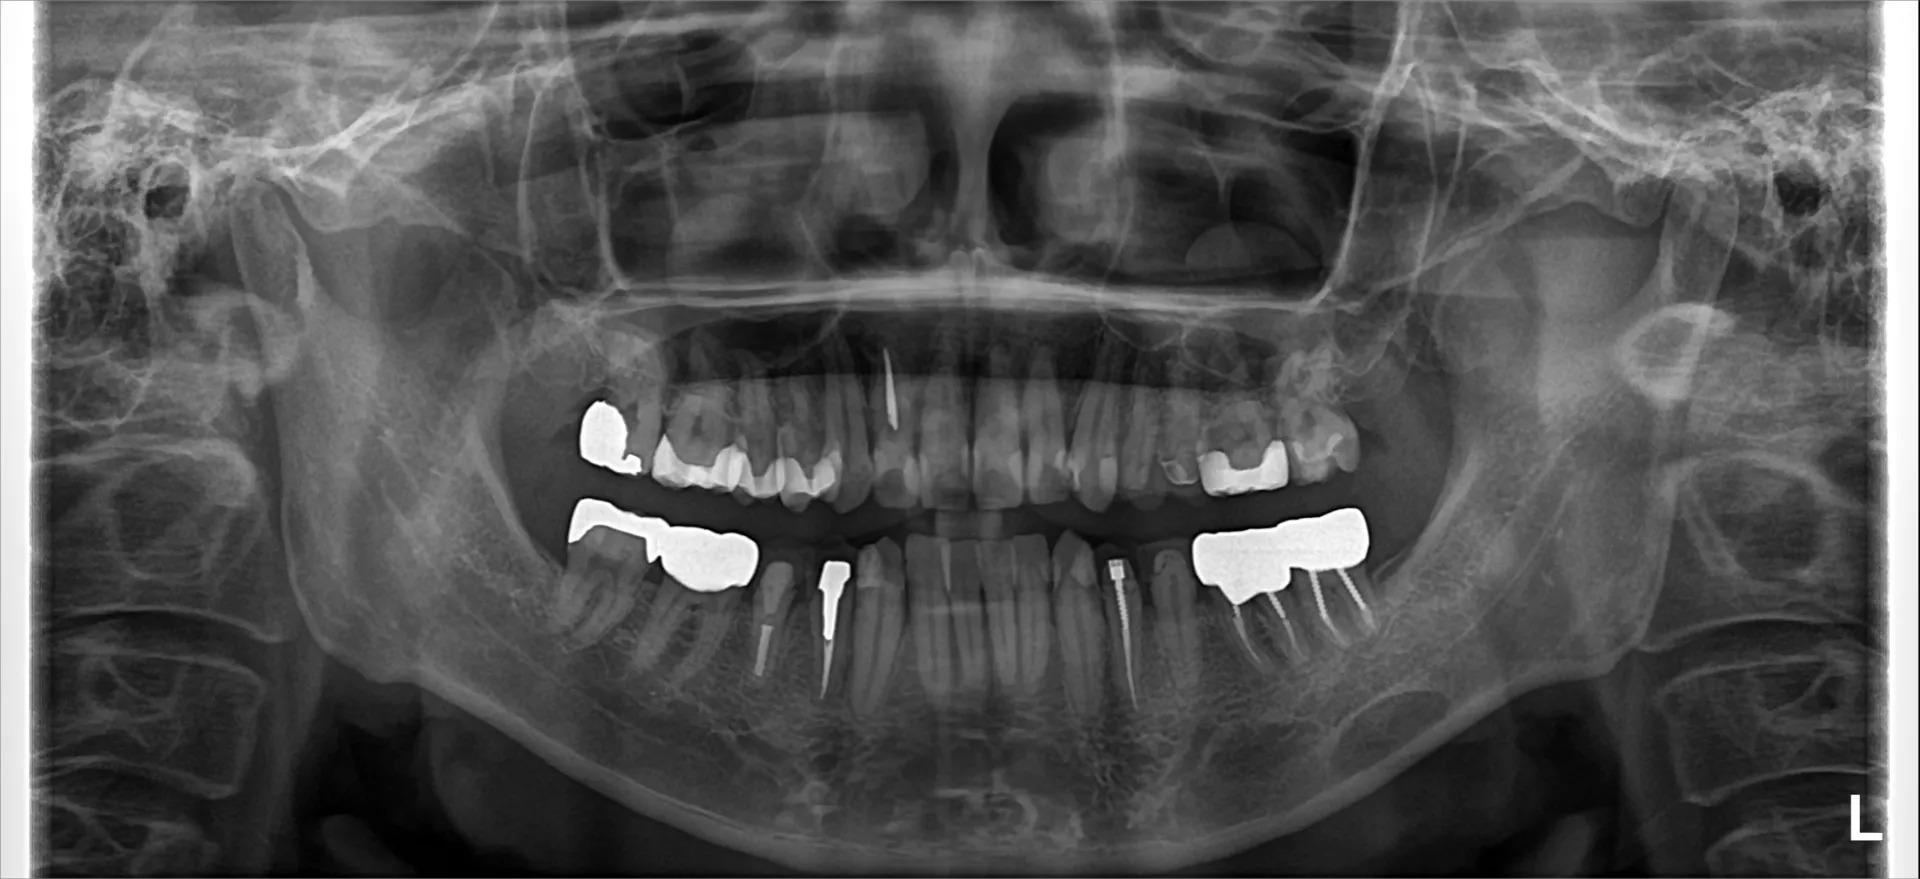

別件でCT撮影を行いましたが、CT撮影でも楕円形の黒い影が写っています。

平面のパノラマレントゲン写真では骨の外側に位置している影なのか骨の中側なのか外側なのかどの位置に存在しているのかが分かりませんでしたが、CT撮影をしたことで骨の内側に今回の影があることが分かりました。

今回は診断名として静止性骨空洞と呼ばれる病気でした。

ただこの疾患は簡単に言えば、ただのくぼみ程度のことがほとんどで病気というほどのものではない状態です。

しかしながら、骨の中などにこのような黒い影がある場合には嚢胞と呼ばれる病気や腫瘍と呼ばれる病気で人体に良くないもののこともあります。

今回はたまたま別件でCT撮影を行いましたが、レントゲン写真は見えない部分での病気を検出するのに十分な検査法であることが改めてわかるものでした。

放射線被爆という観点からレントゲン写真を拒む方もいらっしゃいますが、適切にレントゲン写真を撮影されることも重要だと考えられます。